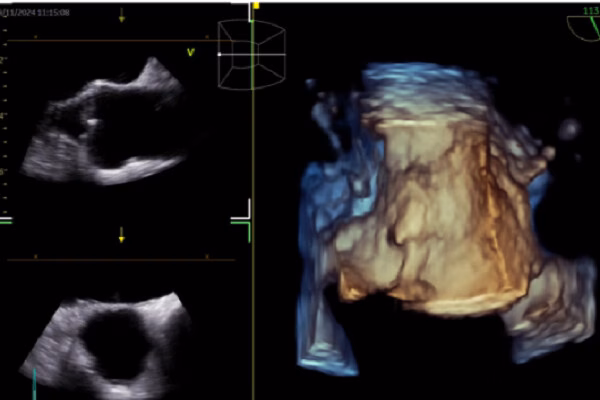

Trong siêu âm tim, AI đóng vai trò quan trọng trong việc nhận diện cấu trúc cơ tim, đo đạc tự động và hỗ trợ báo cáo và chẩn đoán. Công nghệ này không chỉ giúp giảm thiểu sai sót mà còn nâng cao hiệu suất làm việc của bác sĩ. Bên cạnh đó, AI cũng được sử dụng trong CT tim để cải thiện chất lượng hình ảnh, giảm liều xạ và cải thiện dự báo kết cục. Điều này giúp bệnh nhân giảm thiểu rủi ro và đạt được kết quả điều trị tốt hơn.